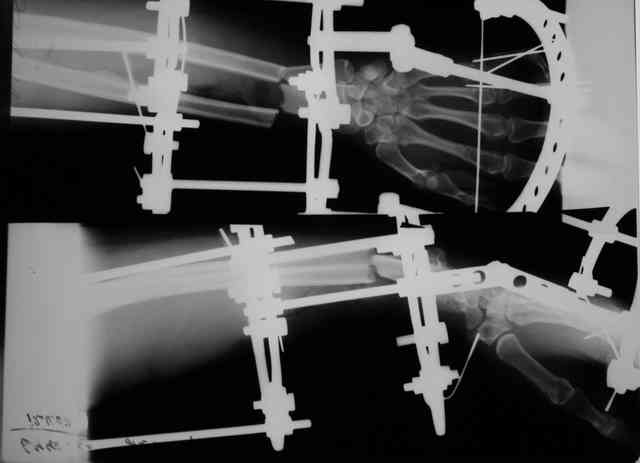

Травма 24 Октября этого года. Диагноз: Неполный травматический отрыв нижней трети предплечья. Выполнено: ПХО открытого перелома, фасциотомия, ЧКДО, шов лучевой артерии. Размозженые мышцы-сгибатели кисти и пальцев экономно иссечены - не сшивались. Спустя месяц выполнена резекция 2,5 см некротизированного конца проксимального отломка лучевой кости. На сегодняшний день по ладонной поверхности предплечья с переходом на наружний край имеется рана с дефектом мягких тканей, выполненная грануляциями с дна и с краев.

По рентгенограммам не видно дефекта лучевой кости после резекции 2,5

см (или снимки до того?).

Прошу прощения - не указал, что после резекции лучевой кости рентгенобследование больной еще не проводилось. На фотогрфиях раны вертикальными черными полосами показаны границы дефекта лучевой кости.